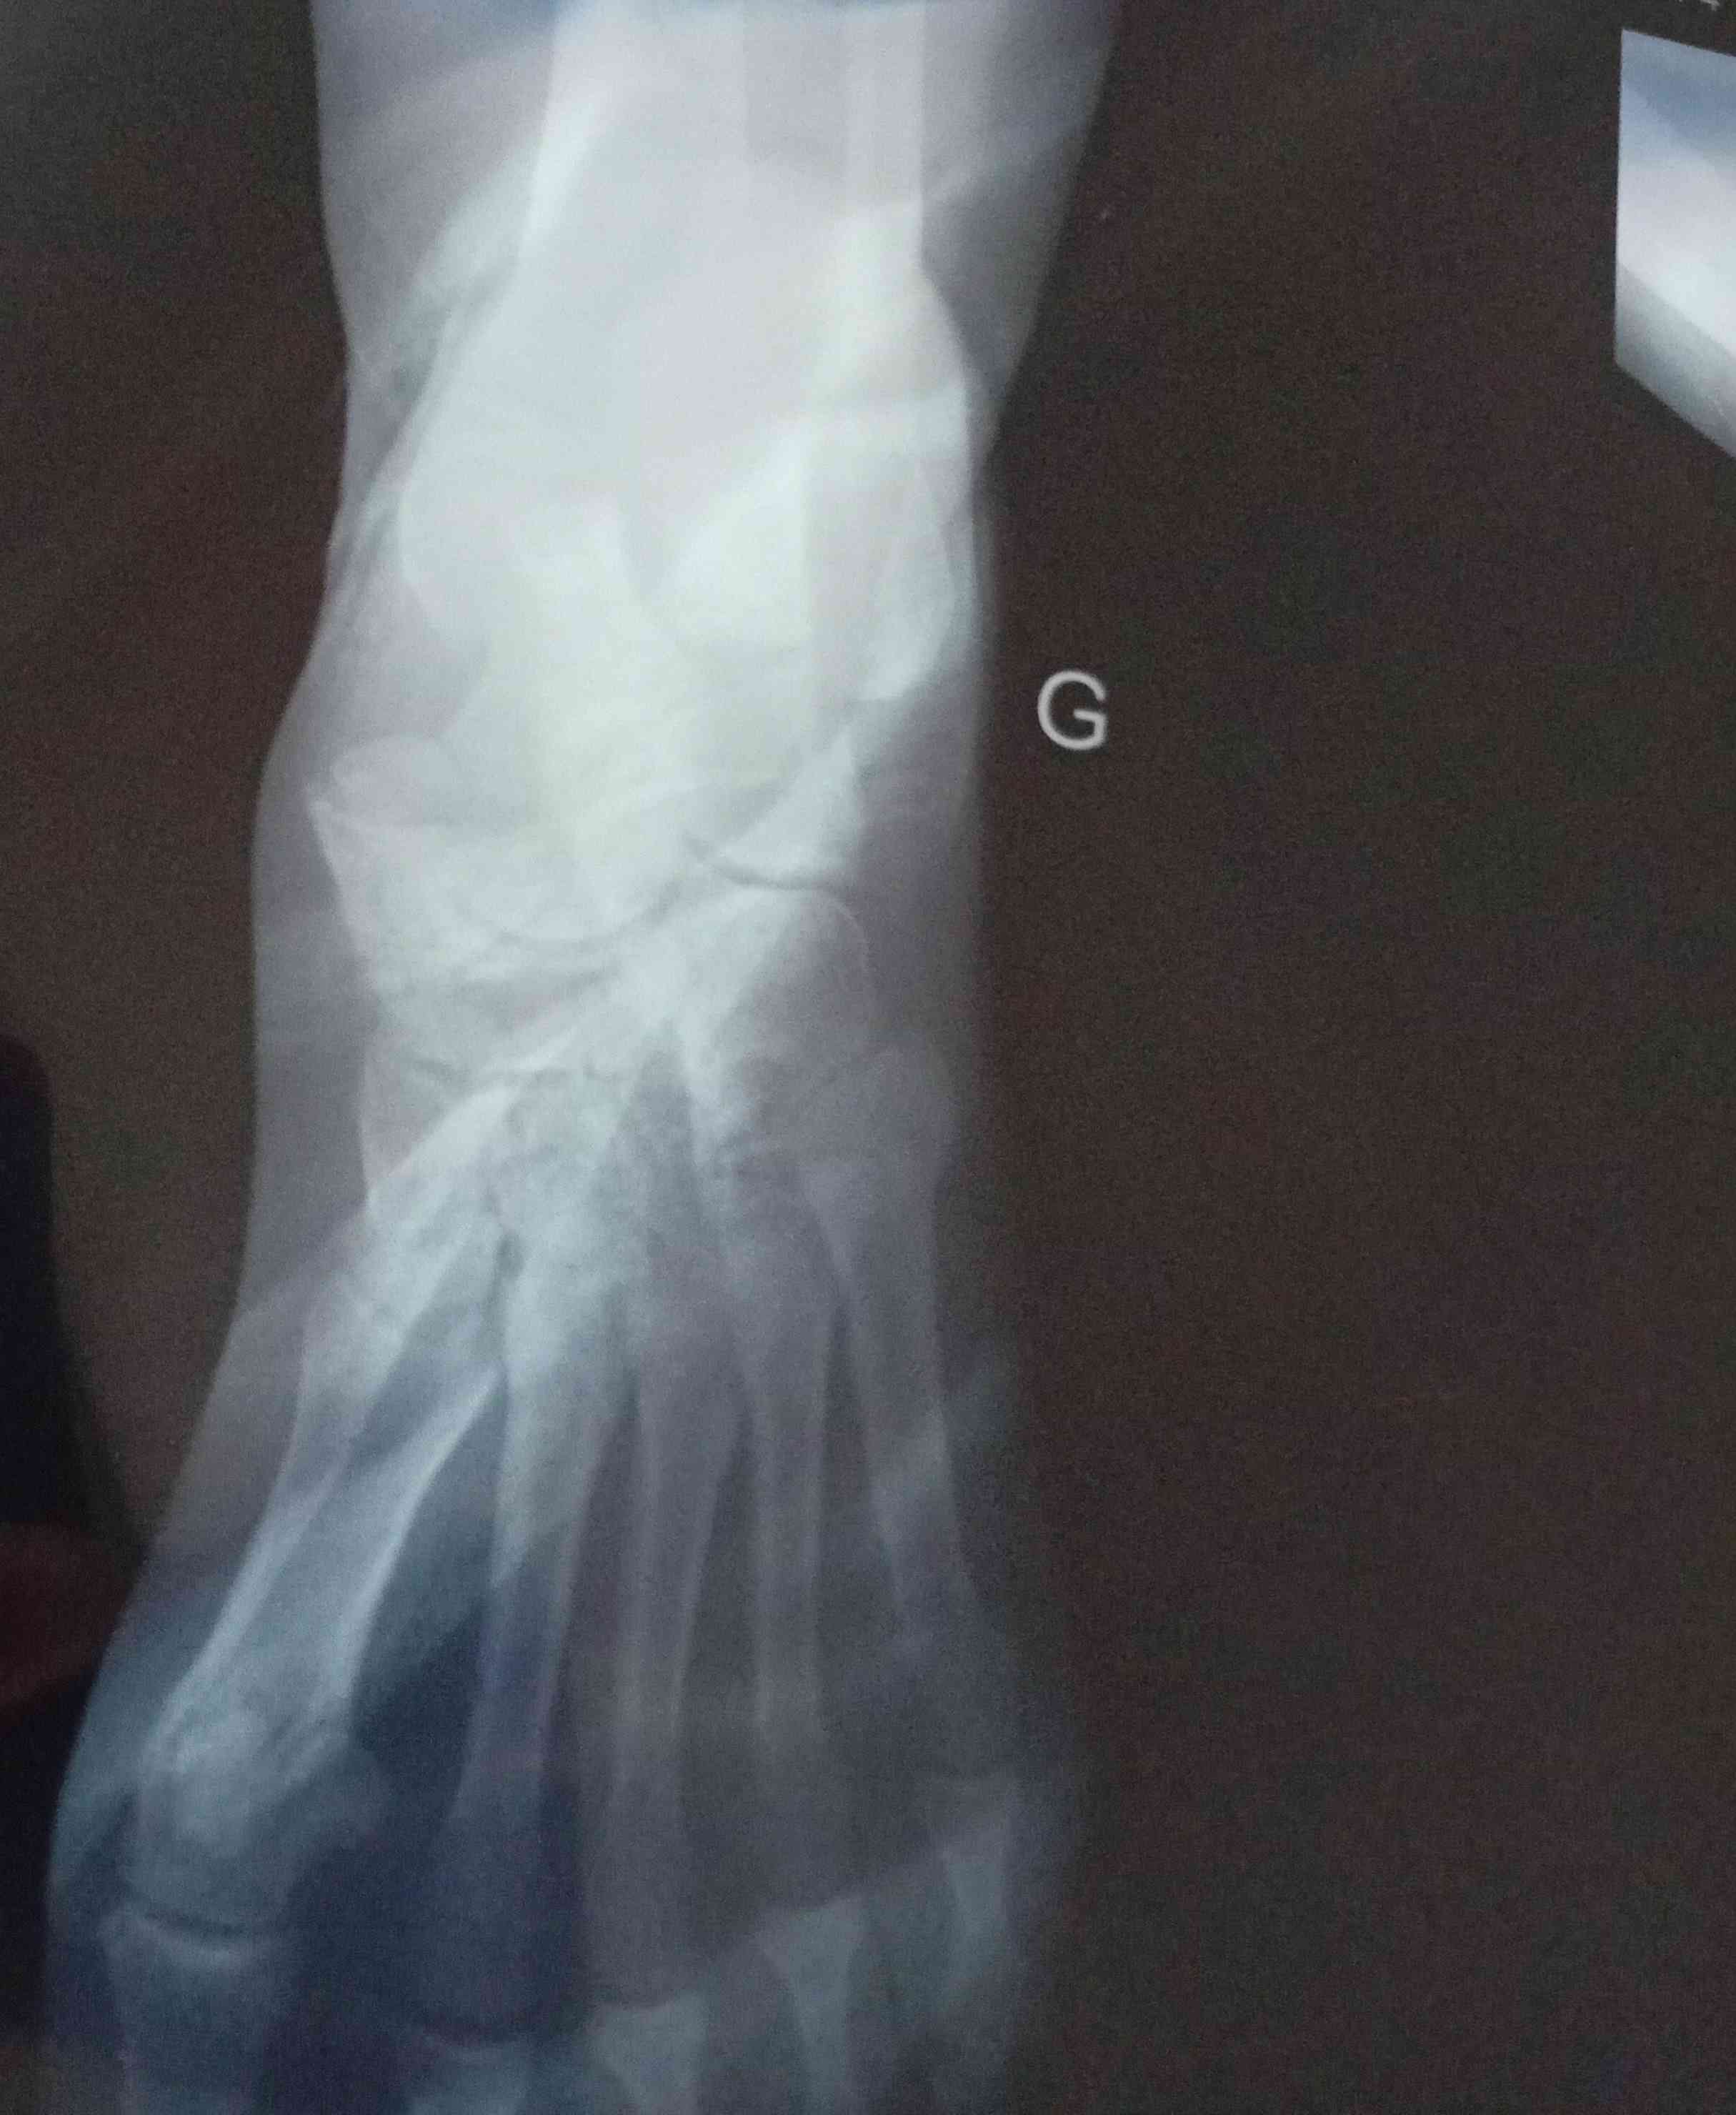

الم الكاحل رغم شفاء الكسر

حدث لدي كسر في كعب القدم منذ 6 سنوات وكما قال الطبيب الكسر التأم ولكن هناك الم وانتفاخ شديد مستمرين...

تم كسر في منطقة الكاحل وبعد ست اسابيع فكيت الجبس اليوم قال لي الدكتور حمل عليها 30% لمدة اسبوعين .....